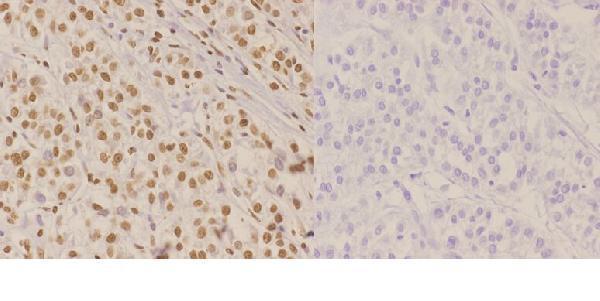

Nucleus. Nucleus, PML body. Chromosome, telomere. Chromosome. Localizes to discrete nuclear foci after treatment with genotoxic agents.